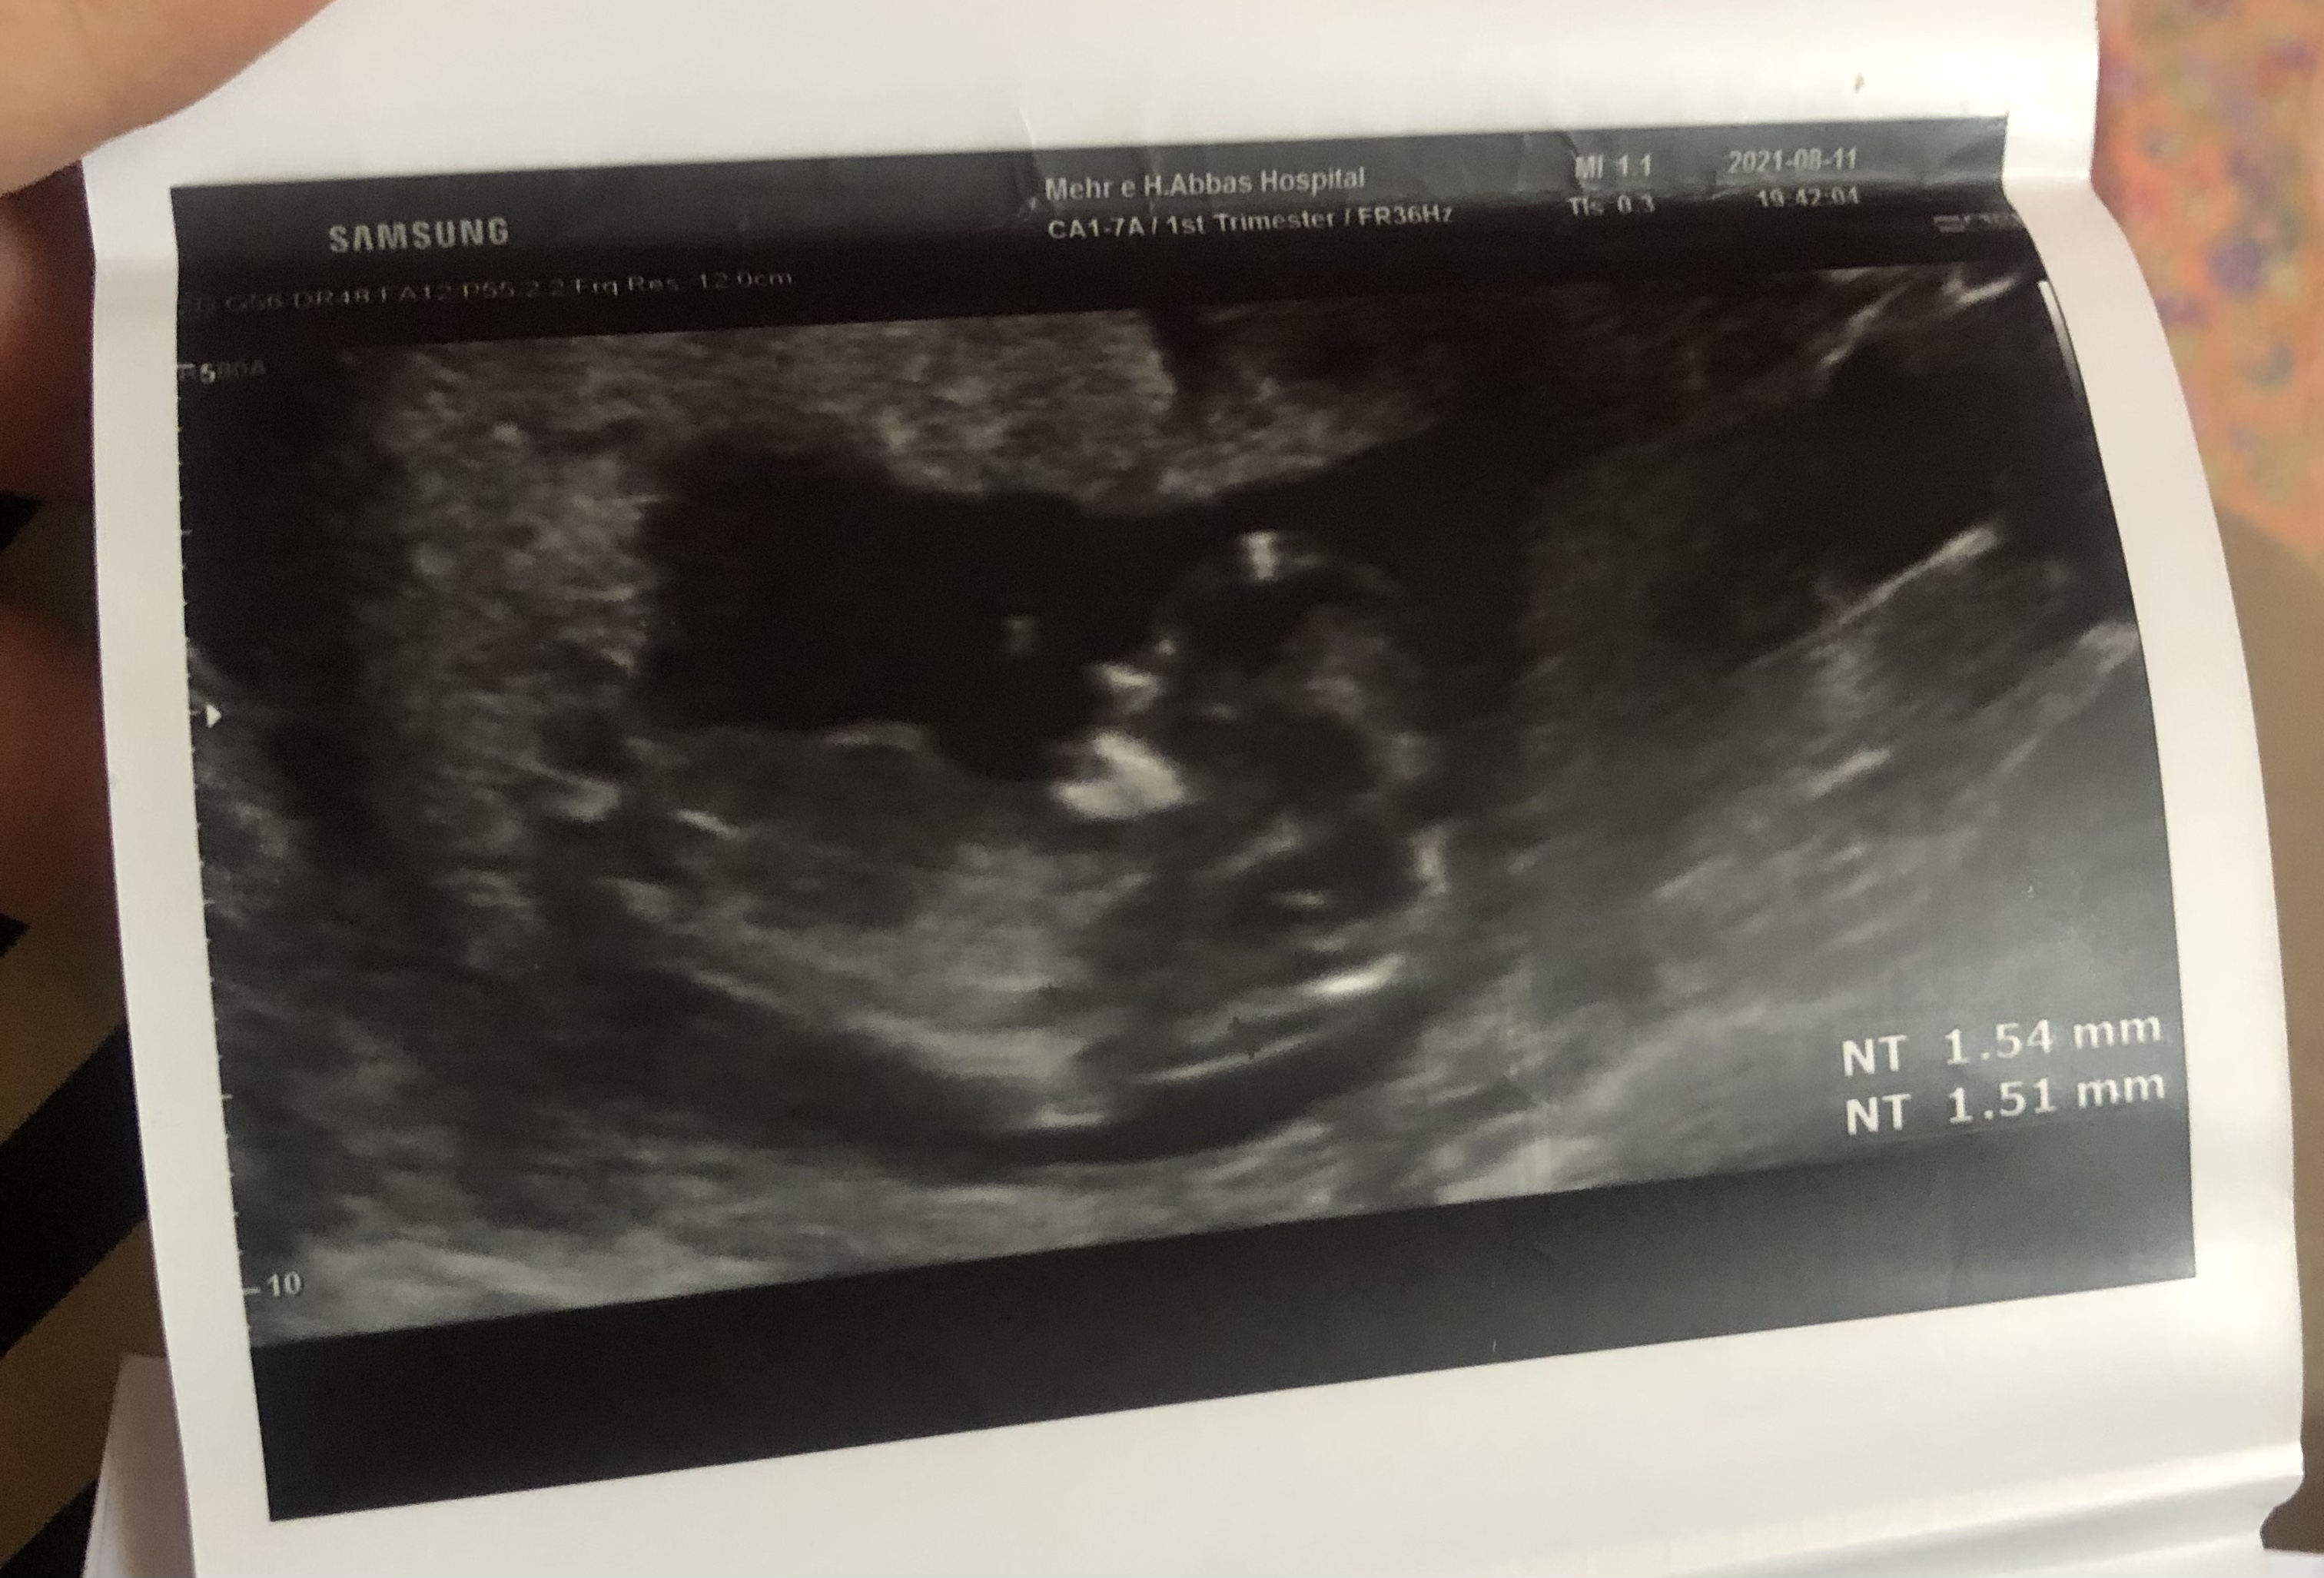

rayti مدیر استارتر عضویت: 1400/06/05 تعداد پست: 1032 دکتر باید می فهمید یه درصد احتمالی رو می تونست بگه احتمال داد باشک گذاشتم عکسشو دخترنازم منتظرتم مامانی

rayti مدیر استارتر عضویت: 1400/06/05 تعداد پست: 1032 عکس دیگه ای نداری؟ ن خیلی واضح نیس عکساش دخترنازم منتظرتم مامانی

rayti مدیر استارتر عضویت: 1400/06/05 تعداد پست: 1032 بنظرم دختره دکتر چی گفت؟؟ گف۸۰درصددختره دخترنازم منتظرتم مامانی